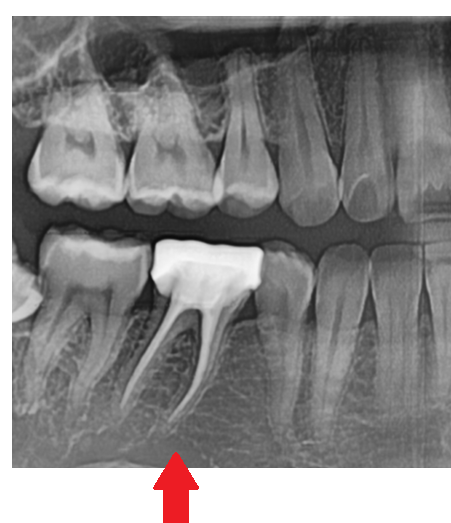

240104 뿌리까지 금이 간 경우

하지만 어금니 치아 부러짐이 발생

깨진 범위가 넓거나 뿌리까지 금이 간 경우,

결국 발치가 불가피할 수 있습니다.

240104 뿌리까지 치아에 금이가고 부러진 경우